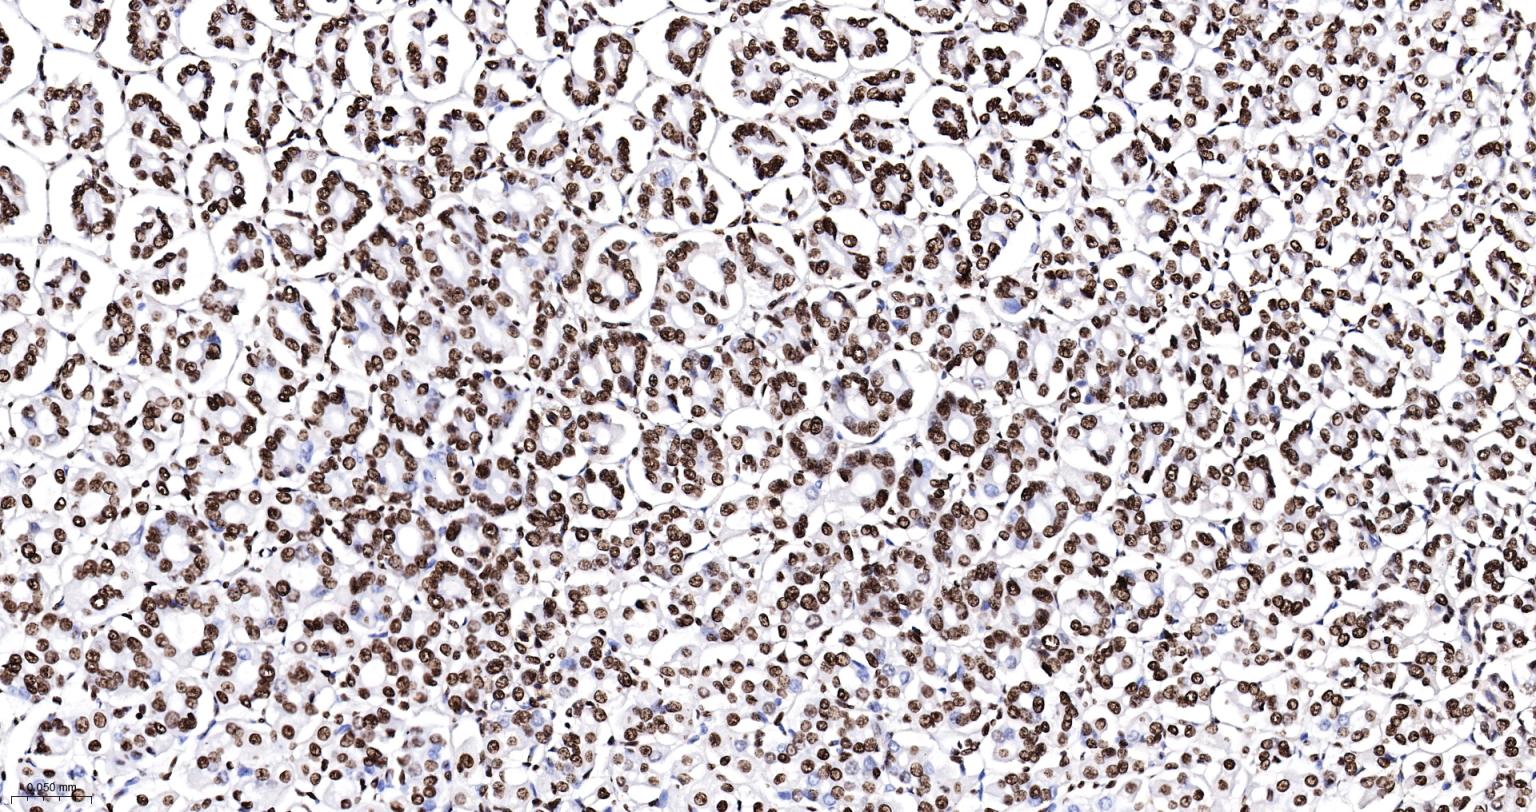

Paraformaldehyde-fixed, paraffin embedded Rat Colon; Antigen retrieval by boiling in sodium citrate buffer (pH6.0) for 15 min; The section was incubated with SFPQ Monoclonal Antibody, Unconjugated (bsm-61746R) at 1:200 overnight at 4°C, followed by conjugation to the bs-0295G-HRP and DAB (C-0010) staining.